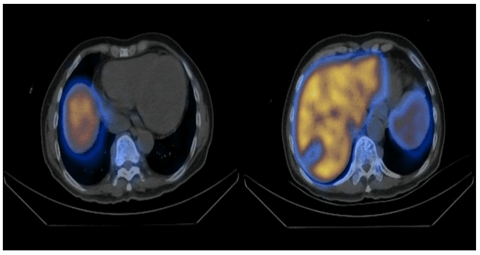

Figure 4: Fused images of the SPECT-CT scan.12.3mCi of Tc-99 nanocolloid was injected intravenously. Segment VII mass shows reduced tracer uptake relative to liver parenchyma. There is also reduced uptake relative to vertebral bone marrow (right).

Paravertebral soft tissue densities are seen along thoracic spine with associated minimal tracer uptake, representing foci of extramedullary haematopoiesis (left).

In view of the inconclusive results, a tc-99m sulphur colloid scan was performed, and it showed a marked lack of uptake (photopaenic area) corresponding to the segment VII lesion in question (Figure 4), suggesting that extramedullary haematopoiesis was an unlikely diagnosis and the lesion remained indeterminate. The patient then underwent a percutaneous biopsy of the segment VII lesion, and the result returned as hepatocellular carcinoma, poorly differentiated. He then underwent wedge resection of segment VI/VII and recovered well post-operatively. The final histology was reported as moderately differentiated hepatocellular carcinoma, 4.2cm in size, on a background of grade 3+ hepatocytic hemosiderosis and bridging fibrosis.

On CT and MRI, HCC has unique tumour characteristics on the critical contrast enhanced phases of the late arterial, portal venous and delayed phases [5]. The classical imaging features of HCC would be arterial phase enhancement with rapid washout as well as a pseudo capsule on portal venous and delayed phases. The presence of these classic features allows the diagnosis of HCC on imaging, significantly reducing the need for percutaneous biopsy [6]. Technitium tc-99m Sulphur Colloid is a gamma-emitting colloid and when injected into the body, is taken up by the reticuloendothelial system. In cases where extramedullary haematopoisis is occurring, sulphur colloid is also taken strongly in these areas, allowing the diagnosis of this condition. The gamma-emission from tc-99m is then picked up by gamma-ray scintillation camera and fused with non-contrast CT images, allowing the areas of extramedullary haematopoisis to be localised.